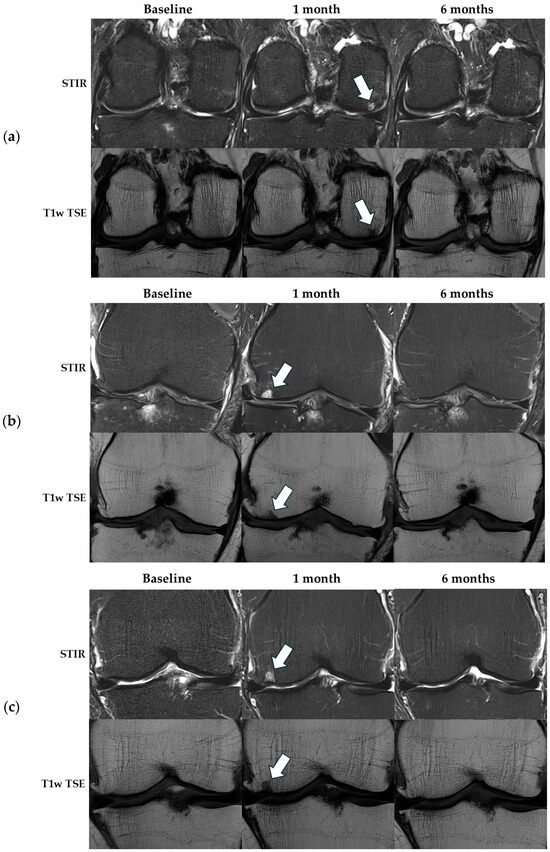

3.2.1. Non-CE-MRI—Effusion-Synovitis

| Non-CE-MRI—MOAKS Effusion-synovitis | X2 (2) = 5.0, p = 0.081 | |||

| Grade 0, n | 1 | 1 | 0 | |

| Grade 1, n | 4 | 6 | 11 | |

| Grade 2, n | 7 | 7 | 3 | |

| Grade 3, n | 5 | 3 | 3 | |